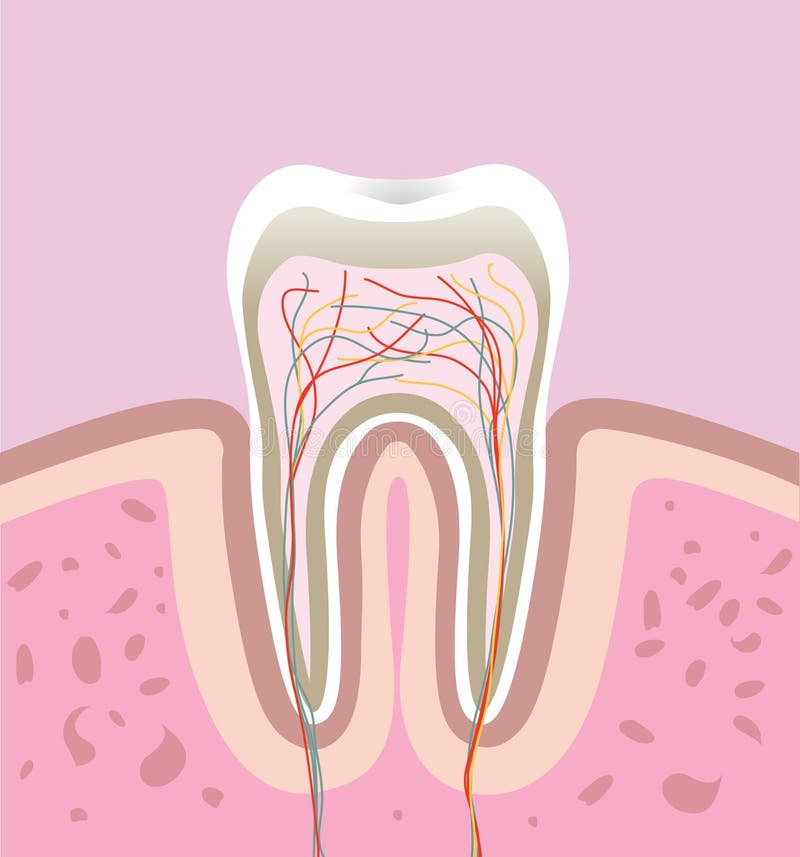

Tanden strukturerar Medicinskt diagram av strukturen av det inre tvärsnittet av tanden